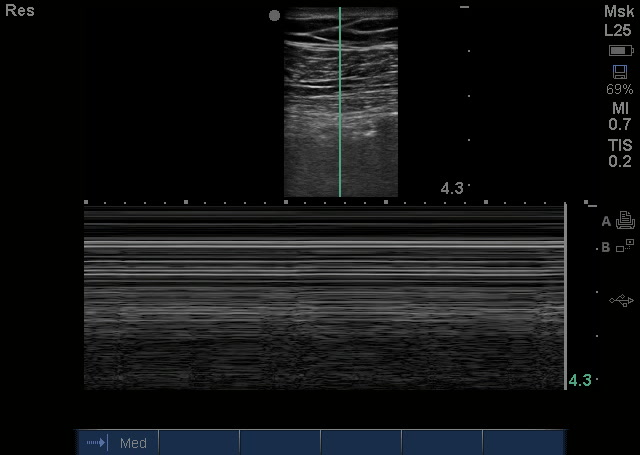

That left side had no lung sliding and a stratosphere sign on M Mode, that’s the first thing that Dr. Chough appreciated, but it was also unclear as to why it was so echogenic (gray) beneath the pleural line. He had no signs of tension pneumothorax on clinical exam, so instead of performing a needle thoracostomy and chest tube, she aborted the rest of the RUSH and ordered a stat Chest XR: